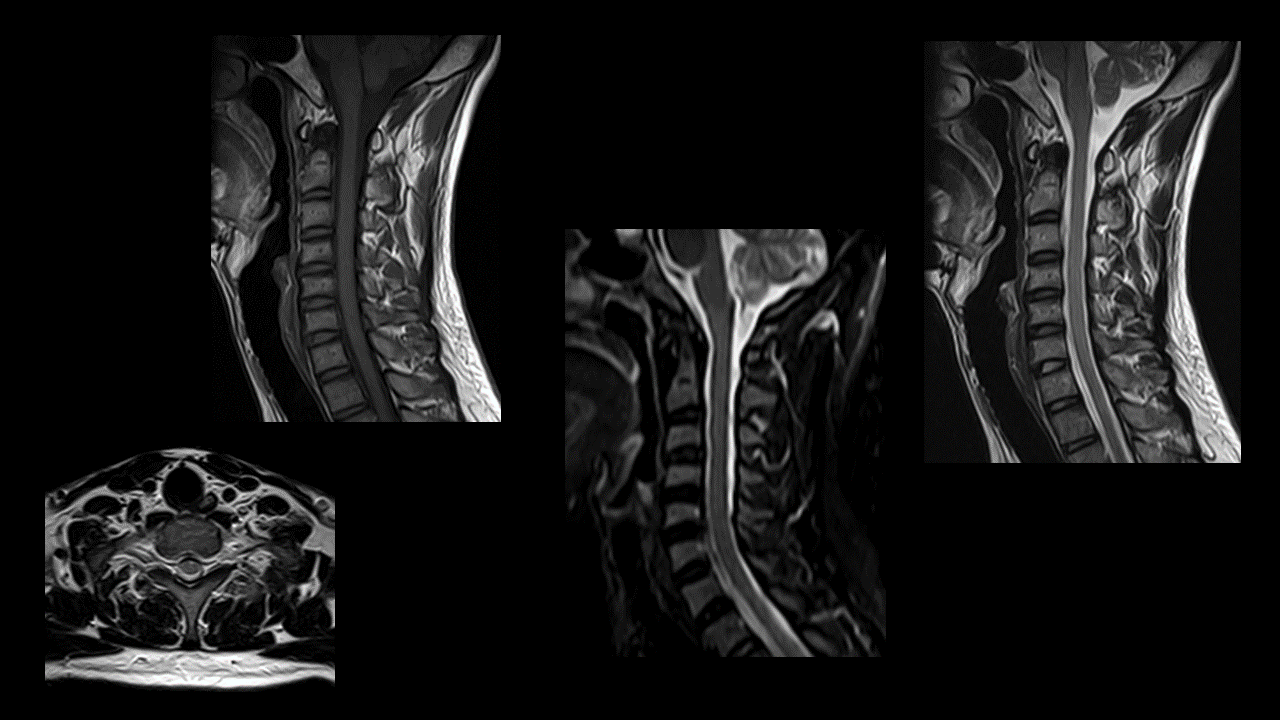

颈椎-T2

颈椎-T1

颈椎-STIR